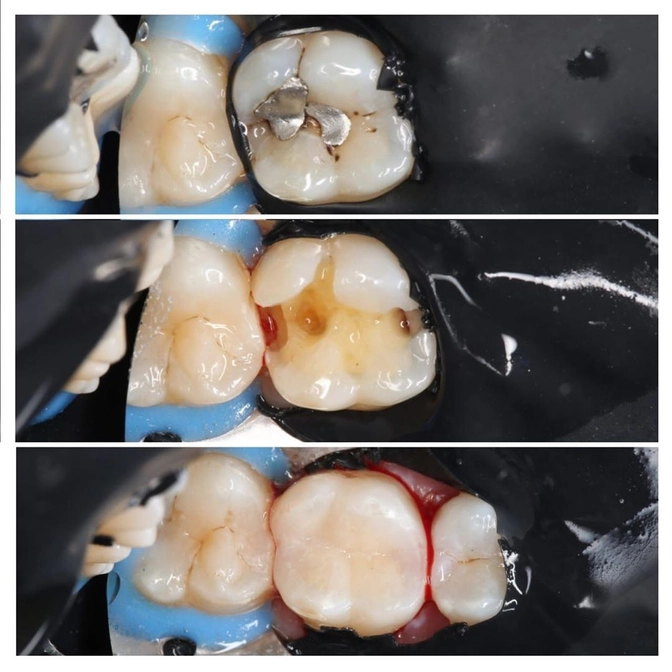

Очередная замена старой несостоятельной пломбы.

Пациент - взрослый, зуб - шестой.

Работу проводила доктор Юлия Яковлева.

На кровь «после» внимание не обращаем.

Обычное дело сразу после при работе «рядом с десной»

Невооруженным глазом видим, что под пломбой и возле нее уже его величество КАРИЕС:

• Старую пломбу убрали;

• КАРИЕС тоже убрали;

• Отреставрировали зуб.

Обратите внимание на вид старой реставрации - это амальгамная пломба.